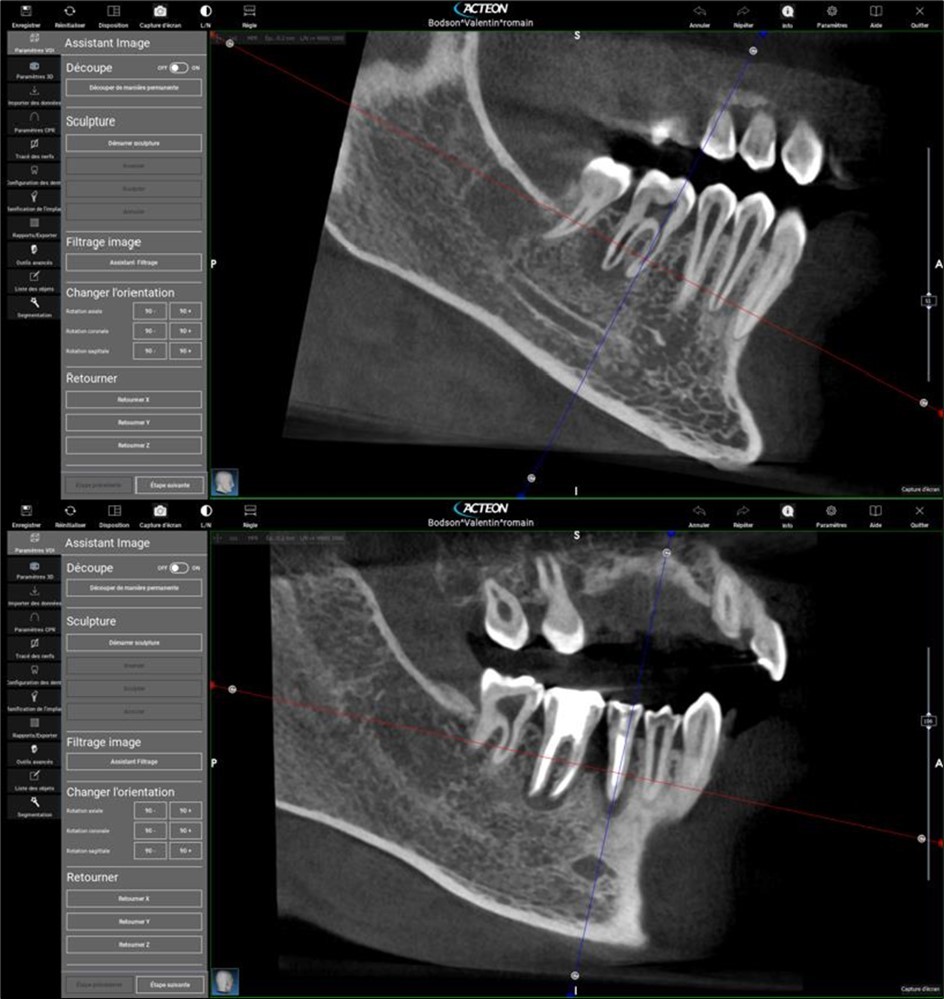

Periapical radiography (phosphorus number 2 plaque and X-MIND® Unity; Acteon) and cone-beam computed tomography (X-MIND® 3D; Acteon) (80 × 80, 150 Micron) were performed and showed periapical lesions on teeth 14, 15, 16, 24, 25, 26, 35, 36, and 46, as well as advanced endo-perio lesions on teeth 26 and 16. orthopantomogram (X-MIND® 3D; Acteon) and bitewings (phosphorus number 2 plaque and X-MIND® Unity; Acteon) also showed wide pulp chambers and roots canals. Figure 1, Figure 2

Figure 2.2. 3, 4, and 5 show periapical lesions on teeth 15, 16, 24, 25, 26, 35, 36, and 46.

2. 3, 4, and 5 show periapical lesions on teeth 15, 16, 24, 25, 26, 35, 36, and 46.

Complete healing of periapical lesions and treatment of teeth 26 and 16 with advanced endo-perio lesions posed challenges due to the patient’s delayed supplementation. In this case, surgical endodontic procedures and the extraction of teeth with advanced endo-perio lesions were considered risky because of the underlying metabolic healing impairment. Figure 3